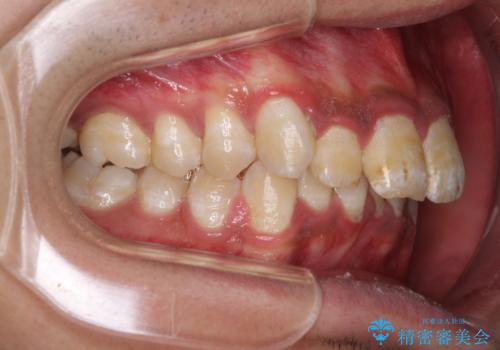

深い咬み合わせと前歯のデコボコ ワイヤー装置での抜歯矯正

- 深い咬み合わせと前歯のデコボコを改善したいとのことで来院された患者様です。

口元の突出感はないものの、上顎前歯のデコボコが著しく、右側の咬み合わせがずれていたため、上顎右側第一小臼歯1本を抜歯することとしました。

咬合力が非常に強く、抜歯したスペースがなかなか閉じないであろうことは予想できましたが、思っていた以上に期間がかかりました。

前歯のすり減りも著しかったため、仕上げの位置の調整にも期間を要しました。